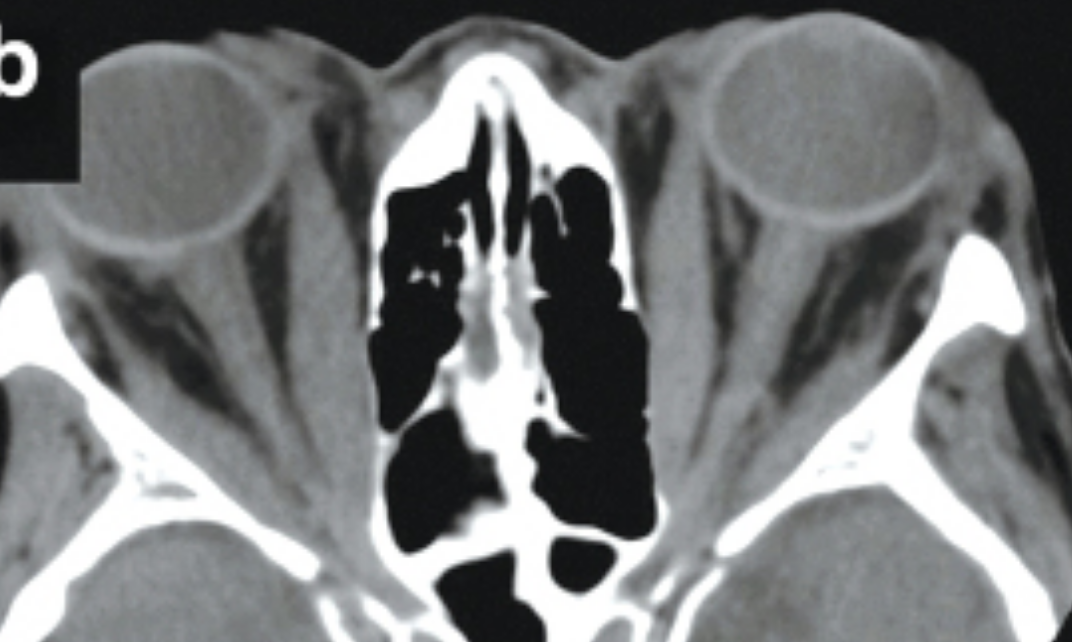

Burch HB, Perros P, Bednarczuk T, et al. Management of Thyroid Eye Disease: A Consensus Statement by the American Thyroid Association and the European Thyroid Association. Thyroid. 2022;32(12):1439-1470. doi:10.1089/thy.2022.0251 (image cropped)

• Thyroid Eye Disease 2^ Graves Disease, OU